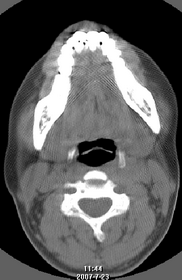

以下是引用还珠格格在2007-7-31 19:32:00的发言:[br]右侧鼻前庭内可见软组织块影,部分鼻中隔包绕其内,邻近骨质未见明显吸收破坏,考虑 1、鼻息肉可能性大 内翻乳头状廇不除外。期待结果。

以下是引用zjzjr在2007-7-31 20:29:00的发言:[br]右侧鼻前庭内可见软组织块影,部分鼻中隔包绕其内,邻近骨质未见明显吸收破坏,考虑 1、鼻息肉可能性大 内翻乳头状廇及肉芽肿类病变除外。期待结果。